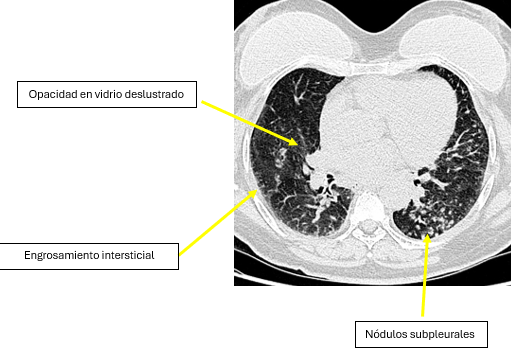

El hallazgo más característico en TC es el engrosamiento de los septos interlobulillares, que puede presentarse de forma lisa, irregular o nodular. Este engrosamiento produce un patrón reticular que delimita los lobulillos pulmonares secundarios.Otro hallazgo frecuente es el engrosamiento del intersticio peribroncovascular, que refleja la infiltración tumoral de los vasos linfáticos que acompañan a las estructuras broncovasculares. Este engrosamiento puede observarse como bandas lineales que siguen el trayecto de los bronquios y vasos pulmonares. La TC también puede mostrar nódulos pulmonares de pequeño tamaño con distribución perilinfática, localizados a lo largo de los septos interlobulillares, en la región subpleural o alrededor de los haces broncovasculares.

En algunos casos pueden identificarse además opacidades en vidrio deslustrado, que reflejan afectación intersticial o alveolar asociada, así como adenopatías mediastínicas o hiliares y derrames pleurales, hallazgos que pueden coexistir con la infiltración linfática pulmonar.